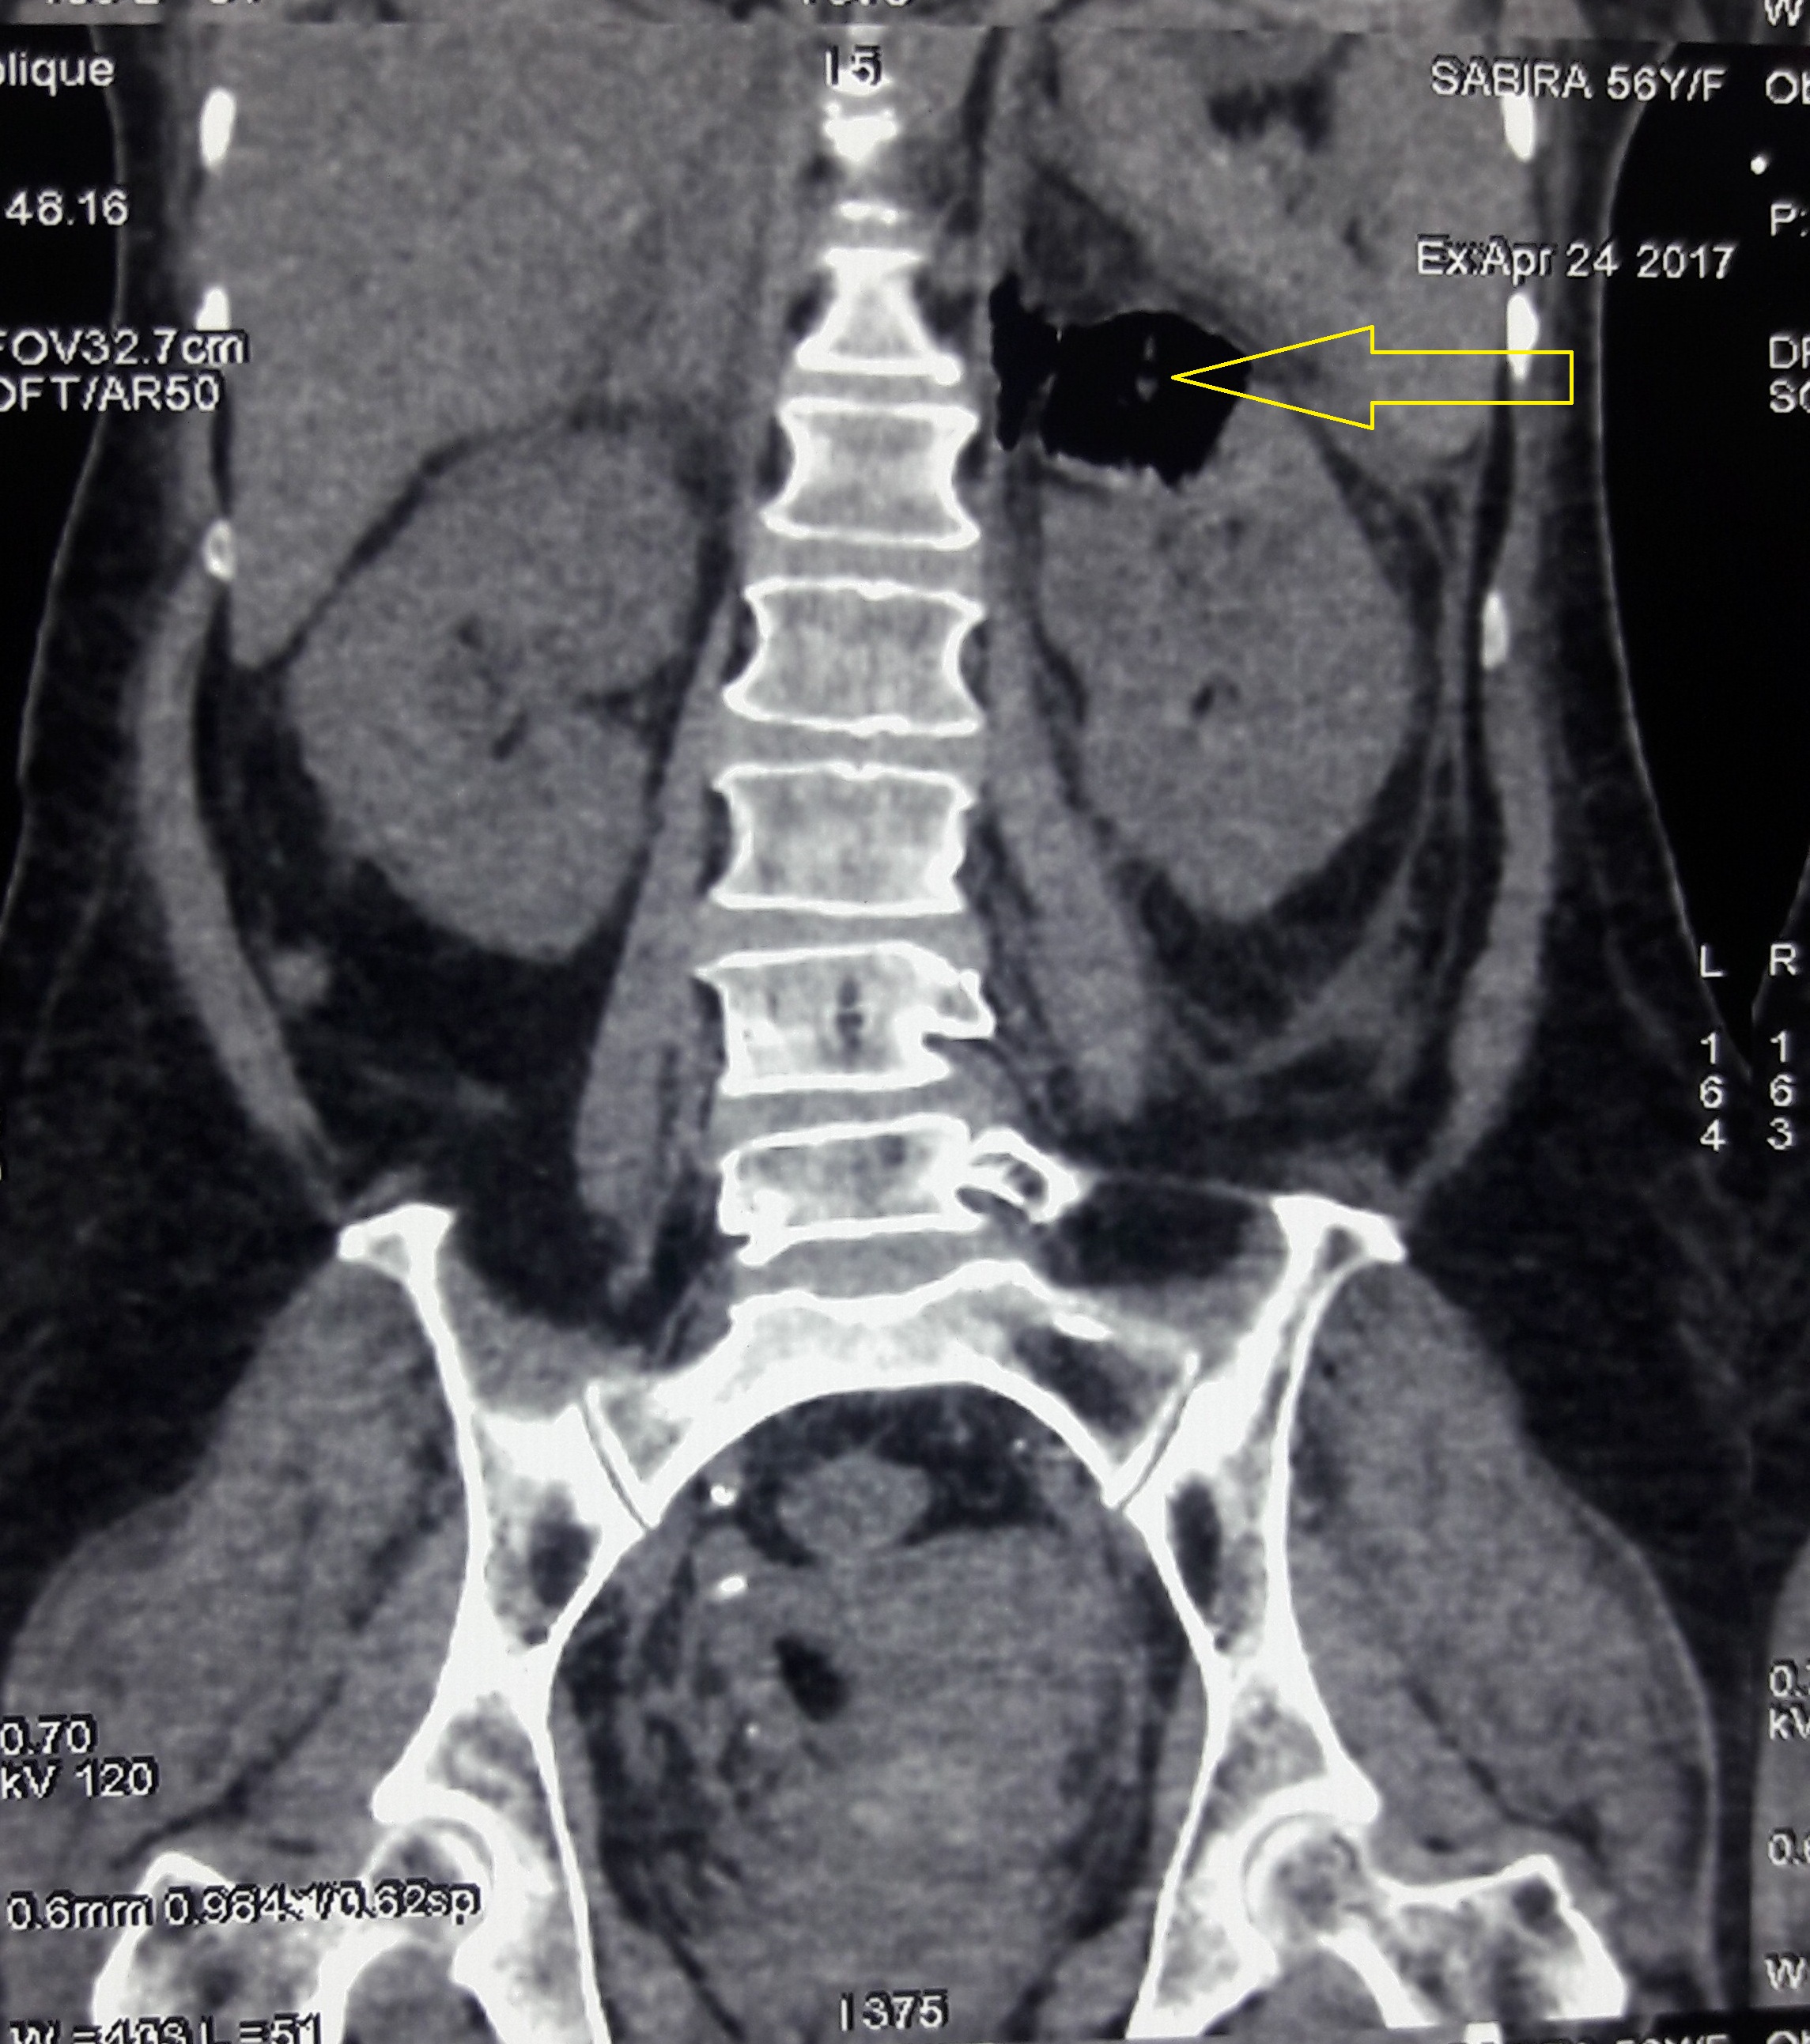

Emphysematous pyelonephritis is a life threatening acute necrotizing infection with associated gas formation involving the renal parenchyma and perinephric tissues. Dengue fever, according to the WHO, is the most rapidly spreading mosquito borne viral infection in the world. Dengue Hemorrgahic Fever is a more severe form of dengue fever and is characterized by fever, bleeding manifestations, plasma leakage and thrombocytopenia. This is a case of a 56 year old female, who presented with history of fever, headache, myalgia and dysuria; and was diagnosed to have emphysematous pyelonephritis with Dengue Hemorrgahic Fever. She was successfully managed with intravenous antibiotics and platelet transfusions, without any urological interventions.